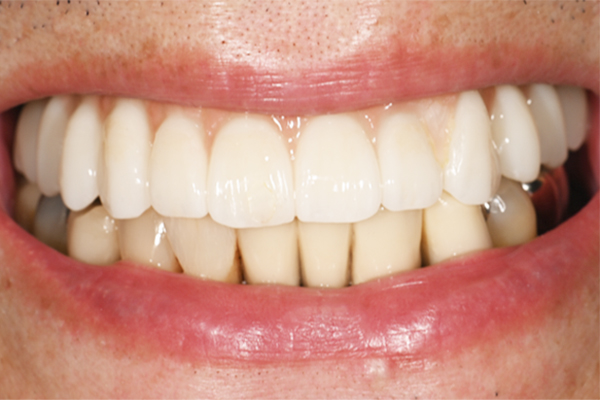

| 主訴 | 上の歯がぐらぐらする |

|---|---|

| 治療内容 | 上顎の歯が重度の歯周病のため全て抜歯し、

上顎に対するインプラント治療を行った。 午前中にインプラントの土台を入れ、夕方に上部構造(歯)を装着。 1日で噛めるようになる治療法。 |

| 治療期間 | 1日 |

| 治療費 | 250万円 |

| 治療 リスク | インプラント治療後2、3日はやや痛みを伴うことがあります。 |